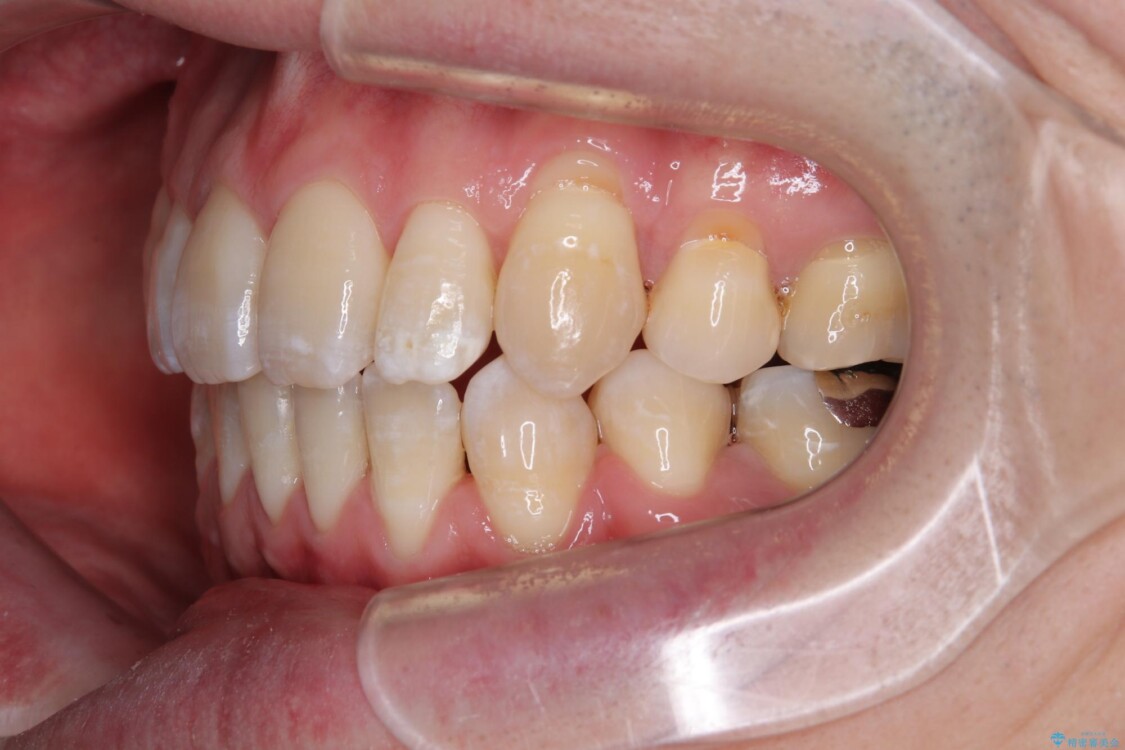

「横から見ると唇が前に出て見えるのが気になる…」 「マスクを外すのが恥ずかしい…」 そんな口元の突出感に悩まれてご来院された患者様。

精密検査の結果、上下左右の小臼歯4本を抜歯し、そのスペースに前歯を後方へ移動させる矯正治療をご提案しました。

装置は、透明感のあるクリアブラケットとホワイトコーティングされたワイヤーを使用した、目立ちにくい審美装置を選択。

周囲に気づかれにくく、日常生活にも自然に溶け込みます。

少しずつ前歯を後ろに下げていくことで、横顔のラインが整い、口元の“出っ張り感”が解消。

治療後には「自然に笑えるようになった」と嬉しいお声をいただきました。